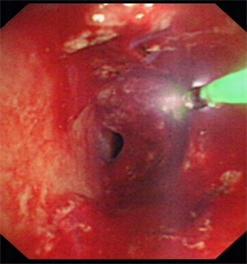

近日我科为一食道癌晚期、食道气道瘘的患者成功放置硅酮支架,患者在禁食1月后终于再次尝到了香甜的米饭,激动万分。该患者1年前在外院确诊为食道癌晚期,一直在我院放化疗科进行化疗及放疗,后患者逐渐出现进食后呛咳,复查胸部CT提示食道癌气道广泛侵袭,存在气道食道瘘可能。患者为避免进食后呛咳,已留置鼻饲,禁食1月。经我科俞万钧副院长会诊,决定为患者进行气道硅酮支架置入堵瘘口,让患者恢复进食。硅酮支架堵瘘术目前国际上开展不多,国内更是寥寥无几,手术难度大,成功率低。手术当日,俞万钧副院长亲自主刀,首先对气道浸润的肿瘤进行消融处理,后成功放置Y型硅酮支架,封堵瘘口。术后次日,患者就能进食流质,再次体会到进食的快乐。利用Y型气道硅酮支架封堵瘘口,全省目前未见报道,全国只有天坛医院,厦门二院等几家医院实施过,这一手术标志着我院硬镜,硅酮支架放置技术达到全国领先水平。(徐涛)